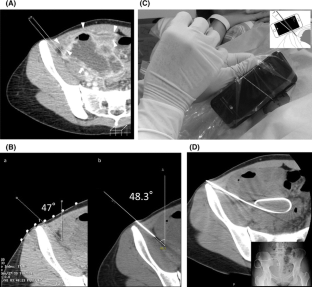

A puncture guideline is displayed by entering the angle into the application. Regardless of the angle at which the device is being held, the motion sensor ensures that the guideline is displayed at the appropriate angle with respect to gravity. The angle of the smartphone’s liquid crystal display (LCD) is also detected, preventing needle deflection from the CT slice image. Physicians can perform the puncture procedure by advancing the needle using the guideline while the smartphone is placed adjacent to the patient. In an experimental puncture test using a sponge as a target, the target was punctured at 30°, 50°, and 70° when the device was tilted to 0°, 15°, 30°, and 45°, respectively. The punctured target was then imaged with a CT scan, and the puncture error was measured.